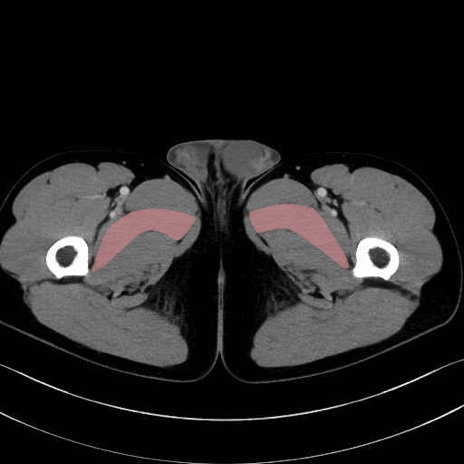

短内転筋(Adductor brevis) のCT画像の解剖

短内転筋 (Adductor brevis)